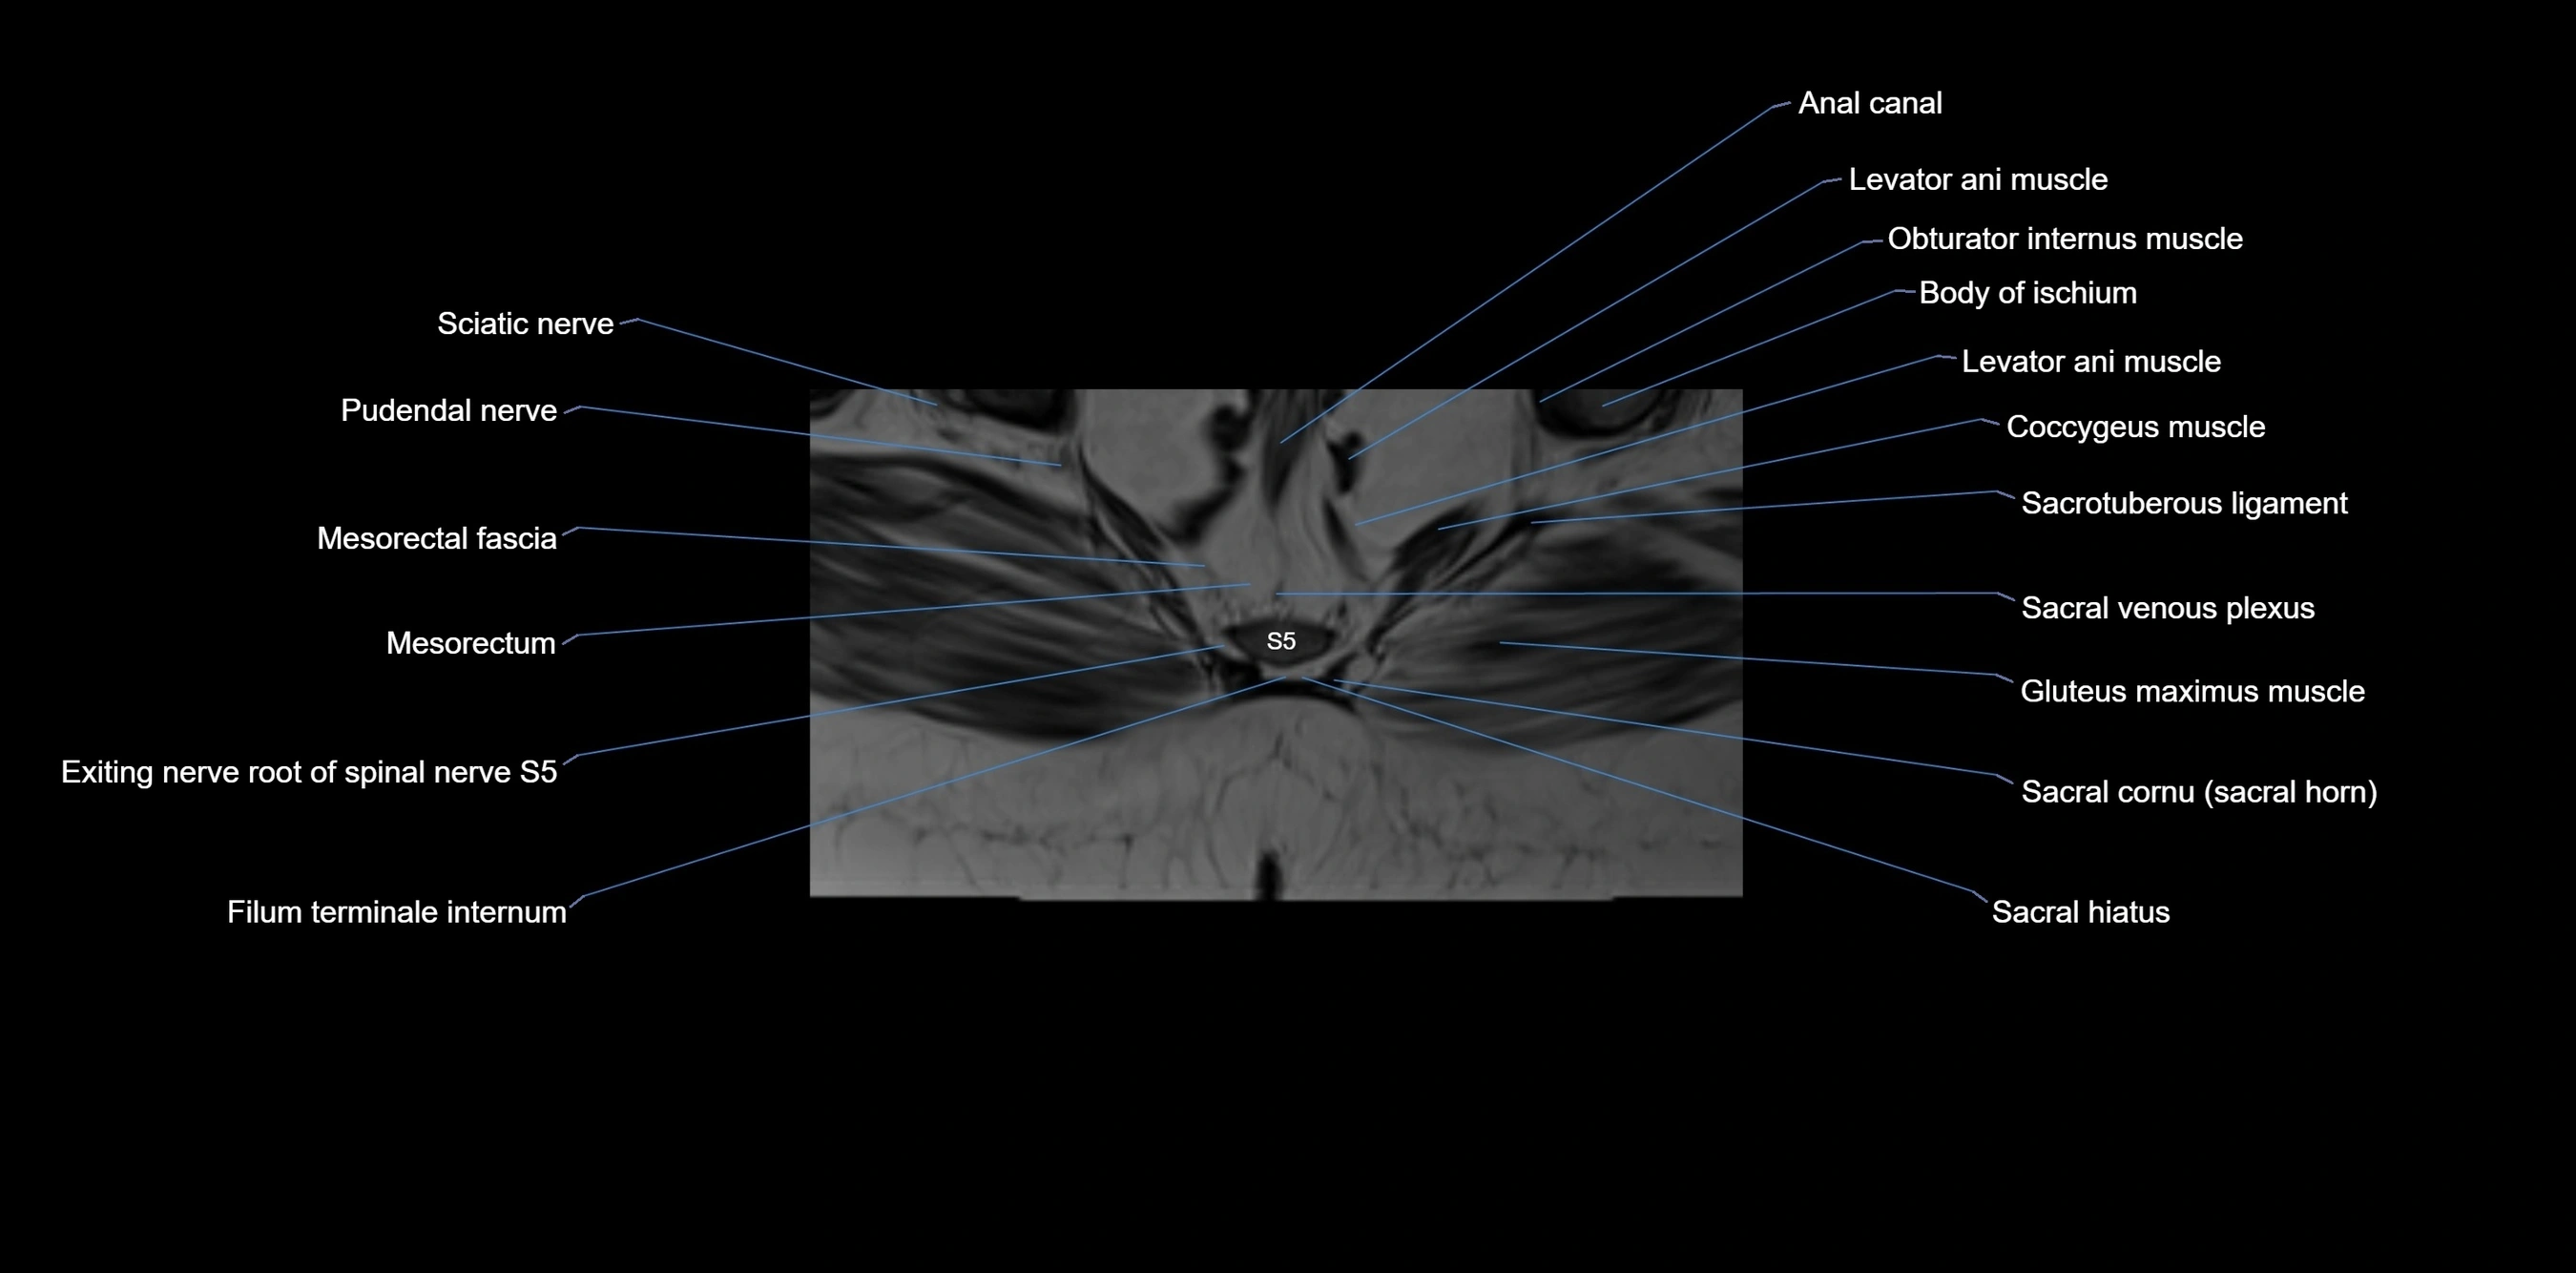

CT image

image